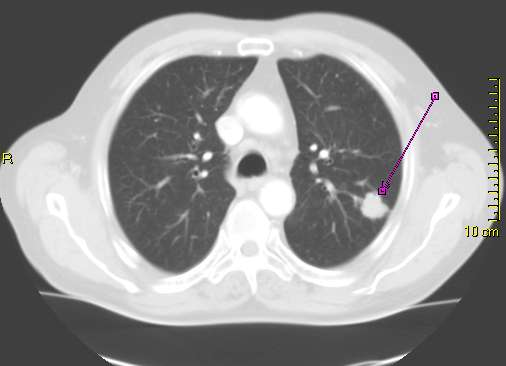

Lung Cancer

Lung Cancer. CT scan showing a cancerous tumor in the left lung. Lange. Not altered. CC BY-SA 3.0

• Low dose computed tomography for adults 50-to-80-years-old with 20 years of smoking history

Low dose CT can be used to detect lung cancer in at risk (smokers) individuals.